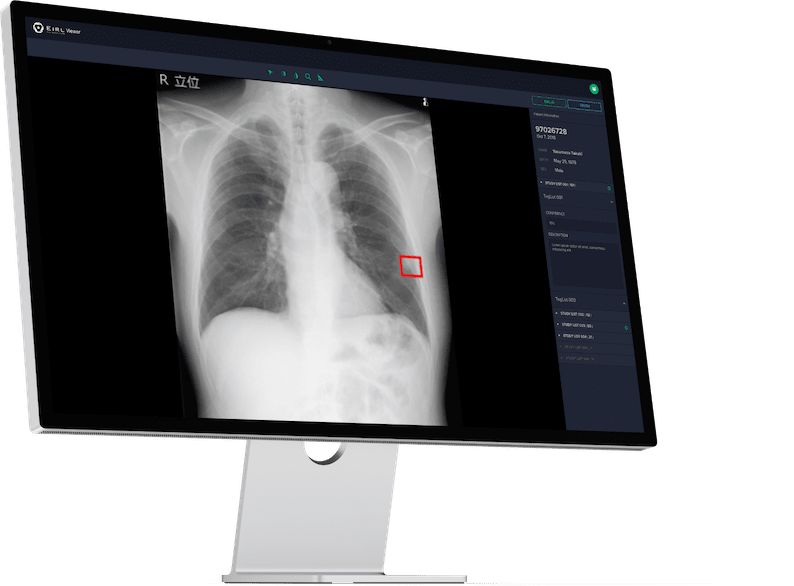

胸部X線画像における包括的な

読影支援を提供

胸部X線画像から肺結節・浸潤影・無気肺・間質性陰影候補を検出する機能に加えて、胸腔内の空気含有面積・肋骨横隔膜角・心胸郭比・縦隔幅・大動脈弓径を自動計測する2つのソフトウェアを統合した新たな製品です。

肺結節検出サポートテクノロジー

胸部X線画像から肺結節に類似した領域(5mm〜30mm) を検出することで、医師による読影をサポートします。本ソフトウェアを併用して読影した場合、医師単独での読影感度45.4%は57.0%に大幅に向上しました(放射線科医:47.1% → 57.1%、非専門医:43.8% → 56.9%)。